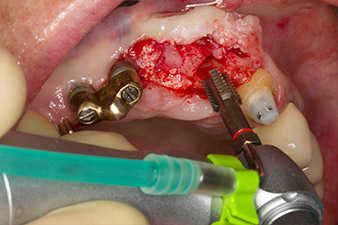

Sección de la rosca con el contra-ángulo WS-75 L

Imagen. 3: Sección de la rosca con el contra-ángulo WS-75 L con una transmisión de 20:1 (programa P4). En este caso, resultan útiles el alto torque del Implantmed, el sistema de sujeción hexagonal para una transmisión segura de la fuerza y la inversión automática del sentido de giro cuando hay una alta resistencia.